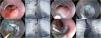

Una semana después de la colocación, presenta hemoptisis en 2 ocasiones y fiebre. Se realiza una revisión endoscópica y se observa el clip Ovesco parcialmente migrado, y por este motivo se procede a su retiro. Se confirma la persistencia de la fístula de 2mm de diámetro. Decidimos realizar cierre endoscópico combinando la técnica de DES y la aplicación de hemoclips. Para esto, se realizó una inyección submucosa a 3mm proximales a la FER, con lo cual se realizó una disección de un área circunferencial de 10mm aproximadamente con un cuchillo tipo I (ERBE, Tubinga, Alemania). Una vez denudada y aislada la FER, se confirma con la aplicación de medio de contraste y su paso hacia la región broncopulmonar derecha, con una guía de 0.035” (Jagwire™, Boston Scientific, Marlborough, MA, EE. UU.). Se realiza una fistulectomía usando el modo Endocut I en efecto 3, para eliminar el epitelio fistuloso con 5mm aproximadamente de profundidad en esta región, y finalmente se realiza el cierre con 3 hemoclips de forma satisfactoria. Se confirma el cierre con la instilación de medio de contraste (fig. 1).

Técnica de cierre de fístula esofagobronquial con disección endoscópica submucosa combinada con hemoclips. A. Persistencia de la fístula tras el retiro del clip OVESCO tipo T a los 22cm de la arcada dentaria superior. B. Confirmación de la fístula por medio de la inyección de medio de contraste. C. Inicio de la disección con inyección submucosa a 3mm proximales a la fístula. D. Fistulectomía endoscópica completa, incluyendo disección a nivel de la muscular propia del esófago. E. Paso de la guía a través de la fístula. F. Imagen fluoroscópica mostrando la guía en región broncopulmonar. G. Colocación de 3 hemoclips para el cierre definitivo. H. Instilación de medio de contraste que confirma el cierre total de la fístula y sin evidencia de paso de contraste a región bronquial.